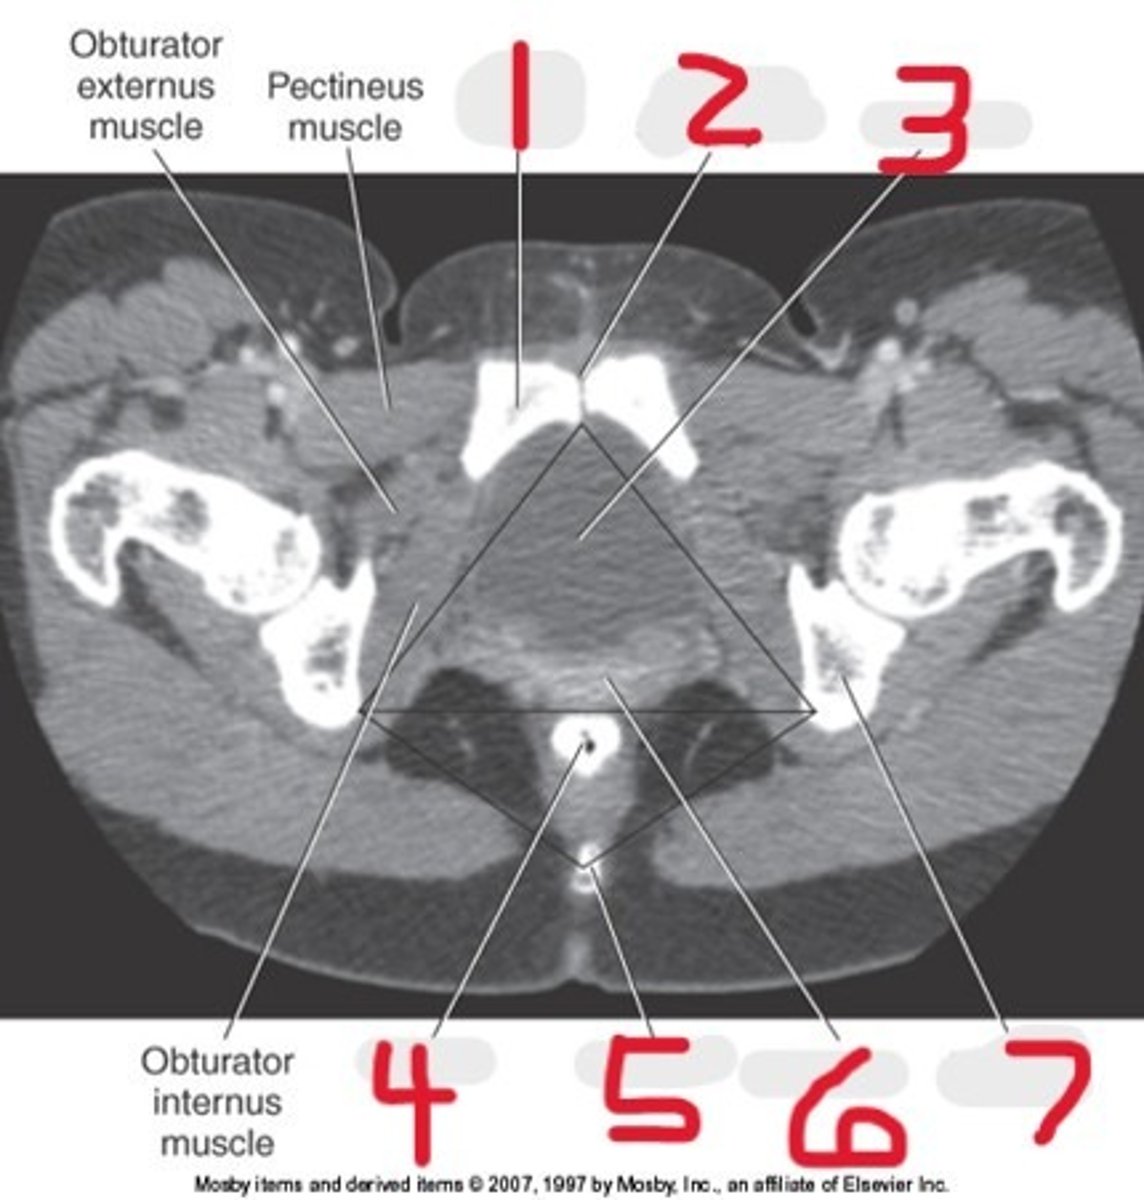

1) SI joint

2) Body

3) Sacral promontory

4) Sacral canal

5) Ilium

6) Lateral mass

7) Articular process

Name all numbered structures